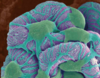

What is a renal calyx?

- Calyces are chambers of the kidney through which urine passes

- Minor calyces surround the apex of the renal pyramids.

- Two or three minor calyces converge to form a major calyx